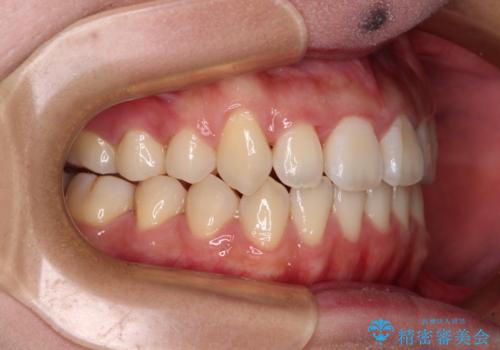

上顎骨を拡大することで、八重歯やデコボコを歯列に収めることができ、下顎の歯が外に位置していた奥歯の咬み合わせも改善することができました。

スペースも短期間に獲得できるため、1年程度で治療を終えることができました。